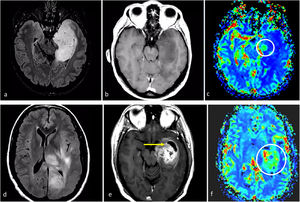

Dos casos de ejemplo en los que los resultados de la biopsia podrían corresponder a un grado histológico 2-3 para un tumor que en realidad sería de grado 4. a-c) Paciente de 57 años. FLAIR axial (a), T1w poscontraste (b) y mapas de color de CBV derivados de DSC-PWI (c). Extensa lesión infiltrante temporal medial izquierda hiperintensa en FLAIR (a), sin realce ni necrosis (b), y un sutil foco nodular de CBV claramente elevado (círculo en c). Es decir, con una biopsia que no captara los focos de CBV elevado se correría el riesgo de subestimar el grado este tumor astrocítico IDH-wildtype como grado 2-3 (NEC) en el estudio anatomopatológico. d-f) Paciente de 58 años. FLAIR axial (d), T1w poscontraste (e) y mapas de color de CBV derivados de DSC-PWI (f). Extensa lesión infiltrante temporal medial izquierda hiperintensa en FLAIR en (d), con un área más focal de realce prominente y necrosis (flecha en e), así como CBV elevado (círculo en f). Es decir, con una biopsia que no captara la necrosis o el componente de CBV elevado se correría el riesgo de subestimar el grado este tumor astrocítico IDH-wildtype como grado 2-3 (NEC) en el estudio anatomopatológico. Se trató a ambos pacientes como glioblastomas IDH-wildtype según la decisión consensuada de un comité de neurooncología.

CBV: volumen sanguíneo cerebral; DSC-PWI: imagen de perfusión dinámica; IDH: gen isocitrato deshidrogenasa; NEC: not elsewhere classified.